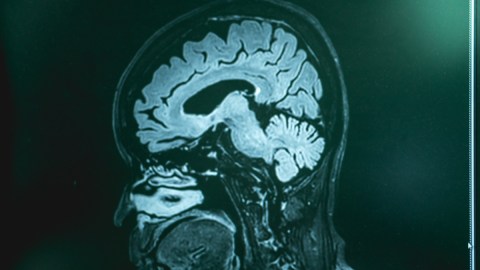

La demencia frontotemporal (DFT), una enfermedad devastadora que afecta partes críticas del cerebro responsable del comportamiento y el lenguaje, ha ganado prominencia recientemente después de que figuras destacadas de la televisión y el cine compartieran sus luchas personales con esta condición.

La DFT, a menudo mal entendida y subdiagnosticada, se manifiesta principalmente en personas de entre 40 y 60 años, y puede resultar en cambios significativos en la personalidad, comportamiento impulsivo e incluso pérdida de la capacidad de comunicación. Los expertos comparan sus síntomas con trastornos de salud mental como la depresión o el trastorno bipolar, lo que dificulta aún más su diagnóstico temprano y preciso.

A pesar de los avances en la comprensión de la enfermedad, las causas exactas de la DFT siguen siendo en gran medida desconocidas. Se cree que el daño a las neuronas desempeña un papel fundamental, con un componente genético que aumenta el riesgo de desarrollar la enfermedad en algunos individuos.